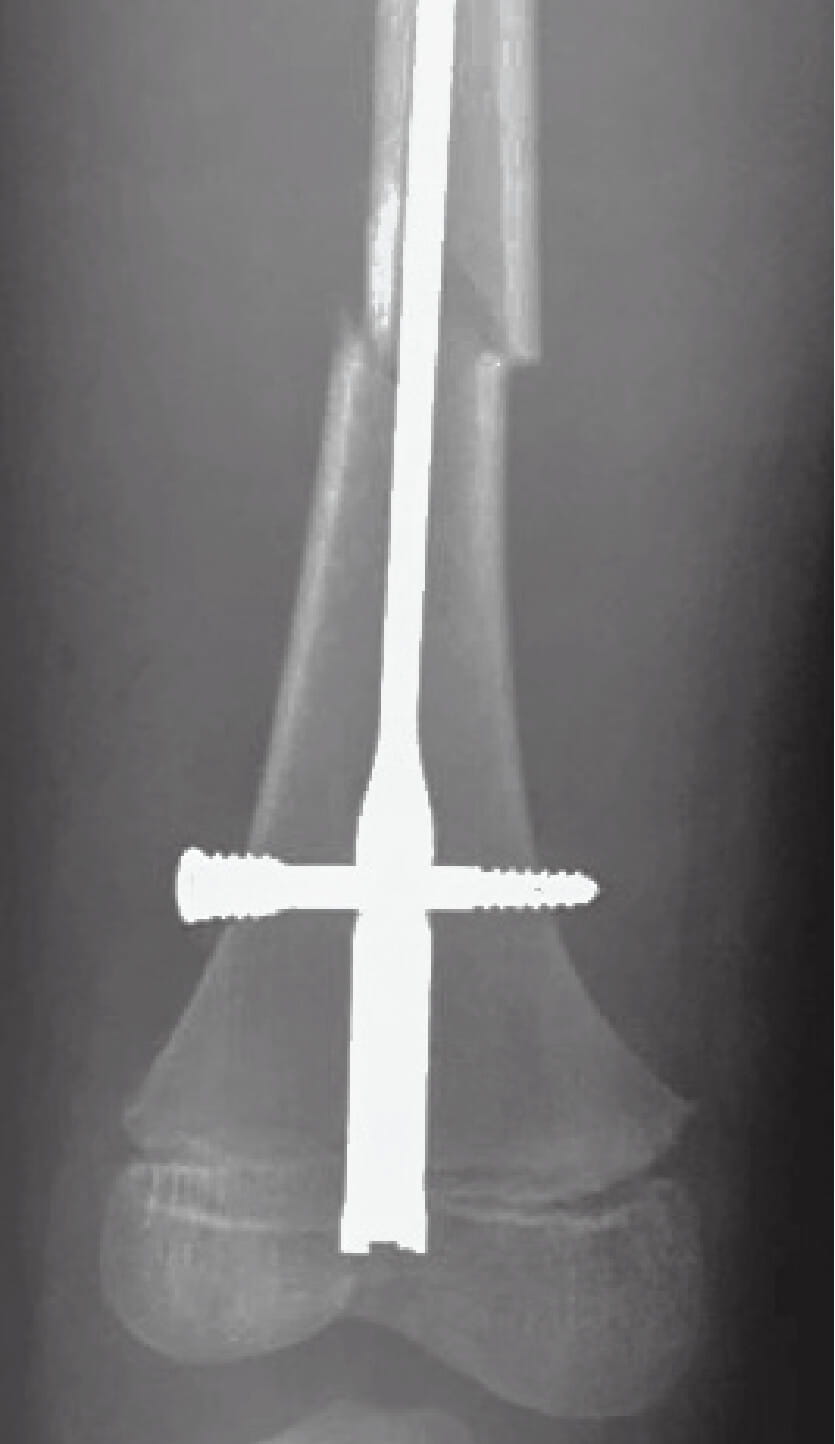

Retrograde femoral nailing involves drilling through the distal femoral physis, the most active lower-extremity growth plate. If that growth plate closes, the child could end up with a severely short or crooked limb. Is it possible, Dr. Liu wondered, to place a large intramedullary nail into this area without damaging the growth plate?

Dr. Liu’s pilot study, published in Journal of Pediatric Orthopaedics, shows it should work under certain conditions. “Our study has demonstrated that the growth plate functions appropriately with a metal rod across it,” Dr. Liu says. “It has also given us parameters to guide the surgeons in these countries in terms of nail sizing and insertion technique.”

Dr. Liu says more research is required before advocating the technique to pediatric surgeons in resource-poor countries. Unlike in the first animal study, a nail placed into a child will change its position relative to the growth plate as the child grows, with the growth plate passing away from the tip of the nail.

However, data from a second sheep study, recently presented at the European Paediatric Orthopaedic Society and Pediatric Orthopaedic Society of North America (POSNA) annual meetings, suggest that growth can slow down after retrograde femoral nailing. Specifically, growth issues are suspect after the growth plate has growth beyond the end of the nail, with microscopic analysis demonstrating small bony bars forming across the growth plate.